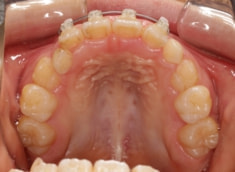

治療後(1年5ヶ月後)